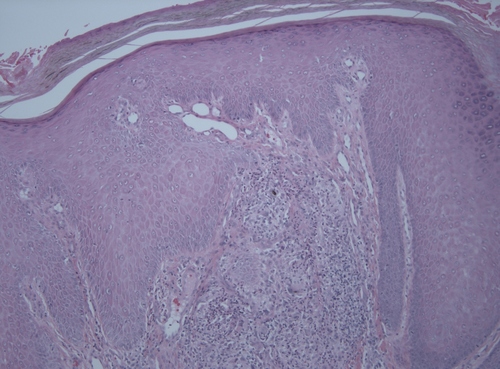

Histologie

La maladie se caractérise par l’apparition de cellules sphériques jaune brunâtre aux parois épaisses et pigmentées. La présence de l'agent est associée à une prolifération et à une hyperplasie de l'épithélium pavimenteux stratifié et à la formation de granulomes mycotiques. Les corps sclérotiques sont à la fois extracellulaires et intracellulaires. La teneur en mélanine des corps sclérotiques pourrait jouer un rôle important dans l'établissement des réponses immunitaires de l'hôte.